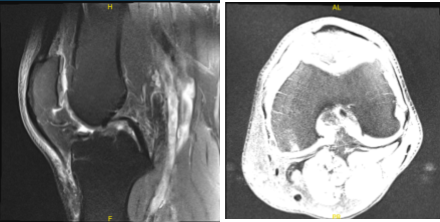

There is mild lateral and patellofemoral arthrosis. There is a large joint effusion. For the left, Moderate-severe medial knee osteoarthritis with broad full-thickness cartilage loss and bone-on-bone apposition. Complex degeneration and tearing of the medial meniscus. Joint effusion with synovitis/debris.

MRI-3T Left knee non-contrast